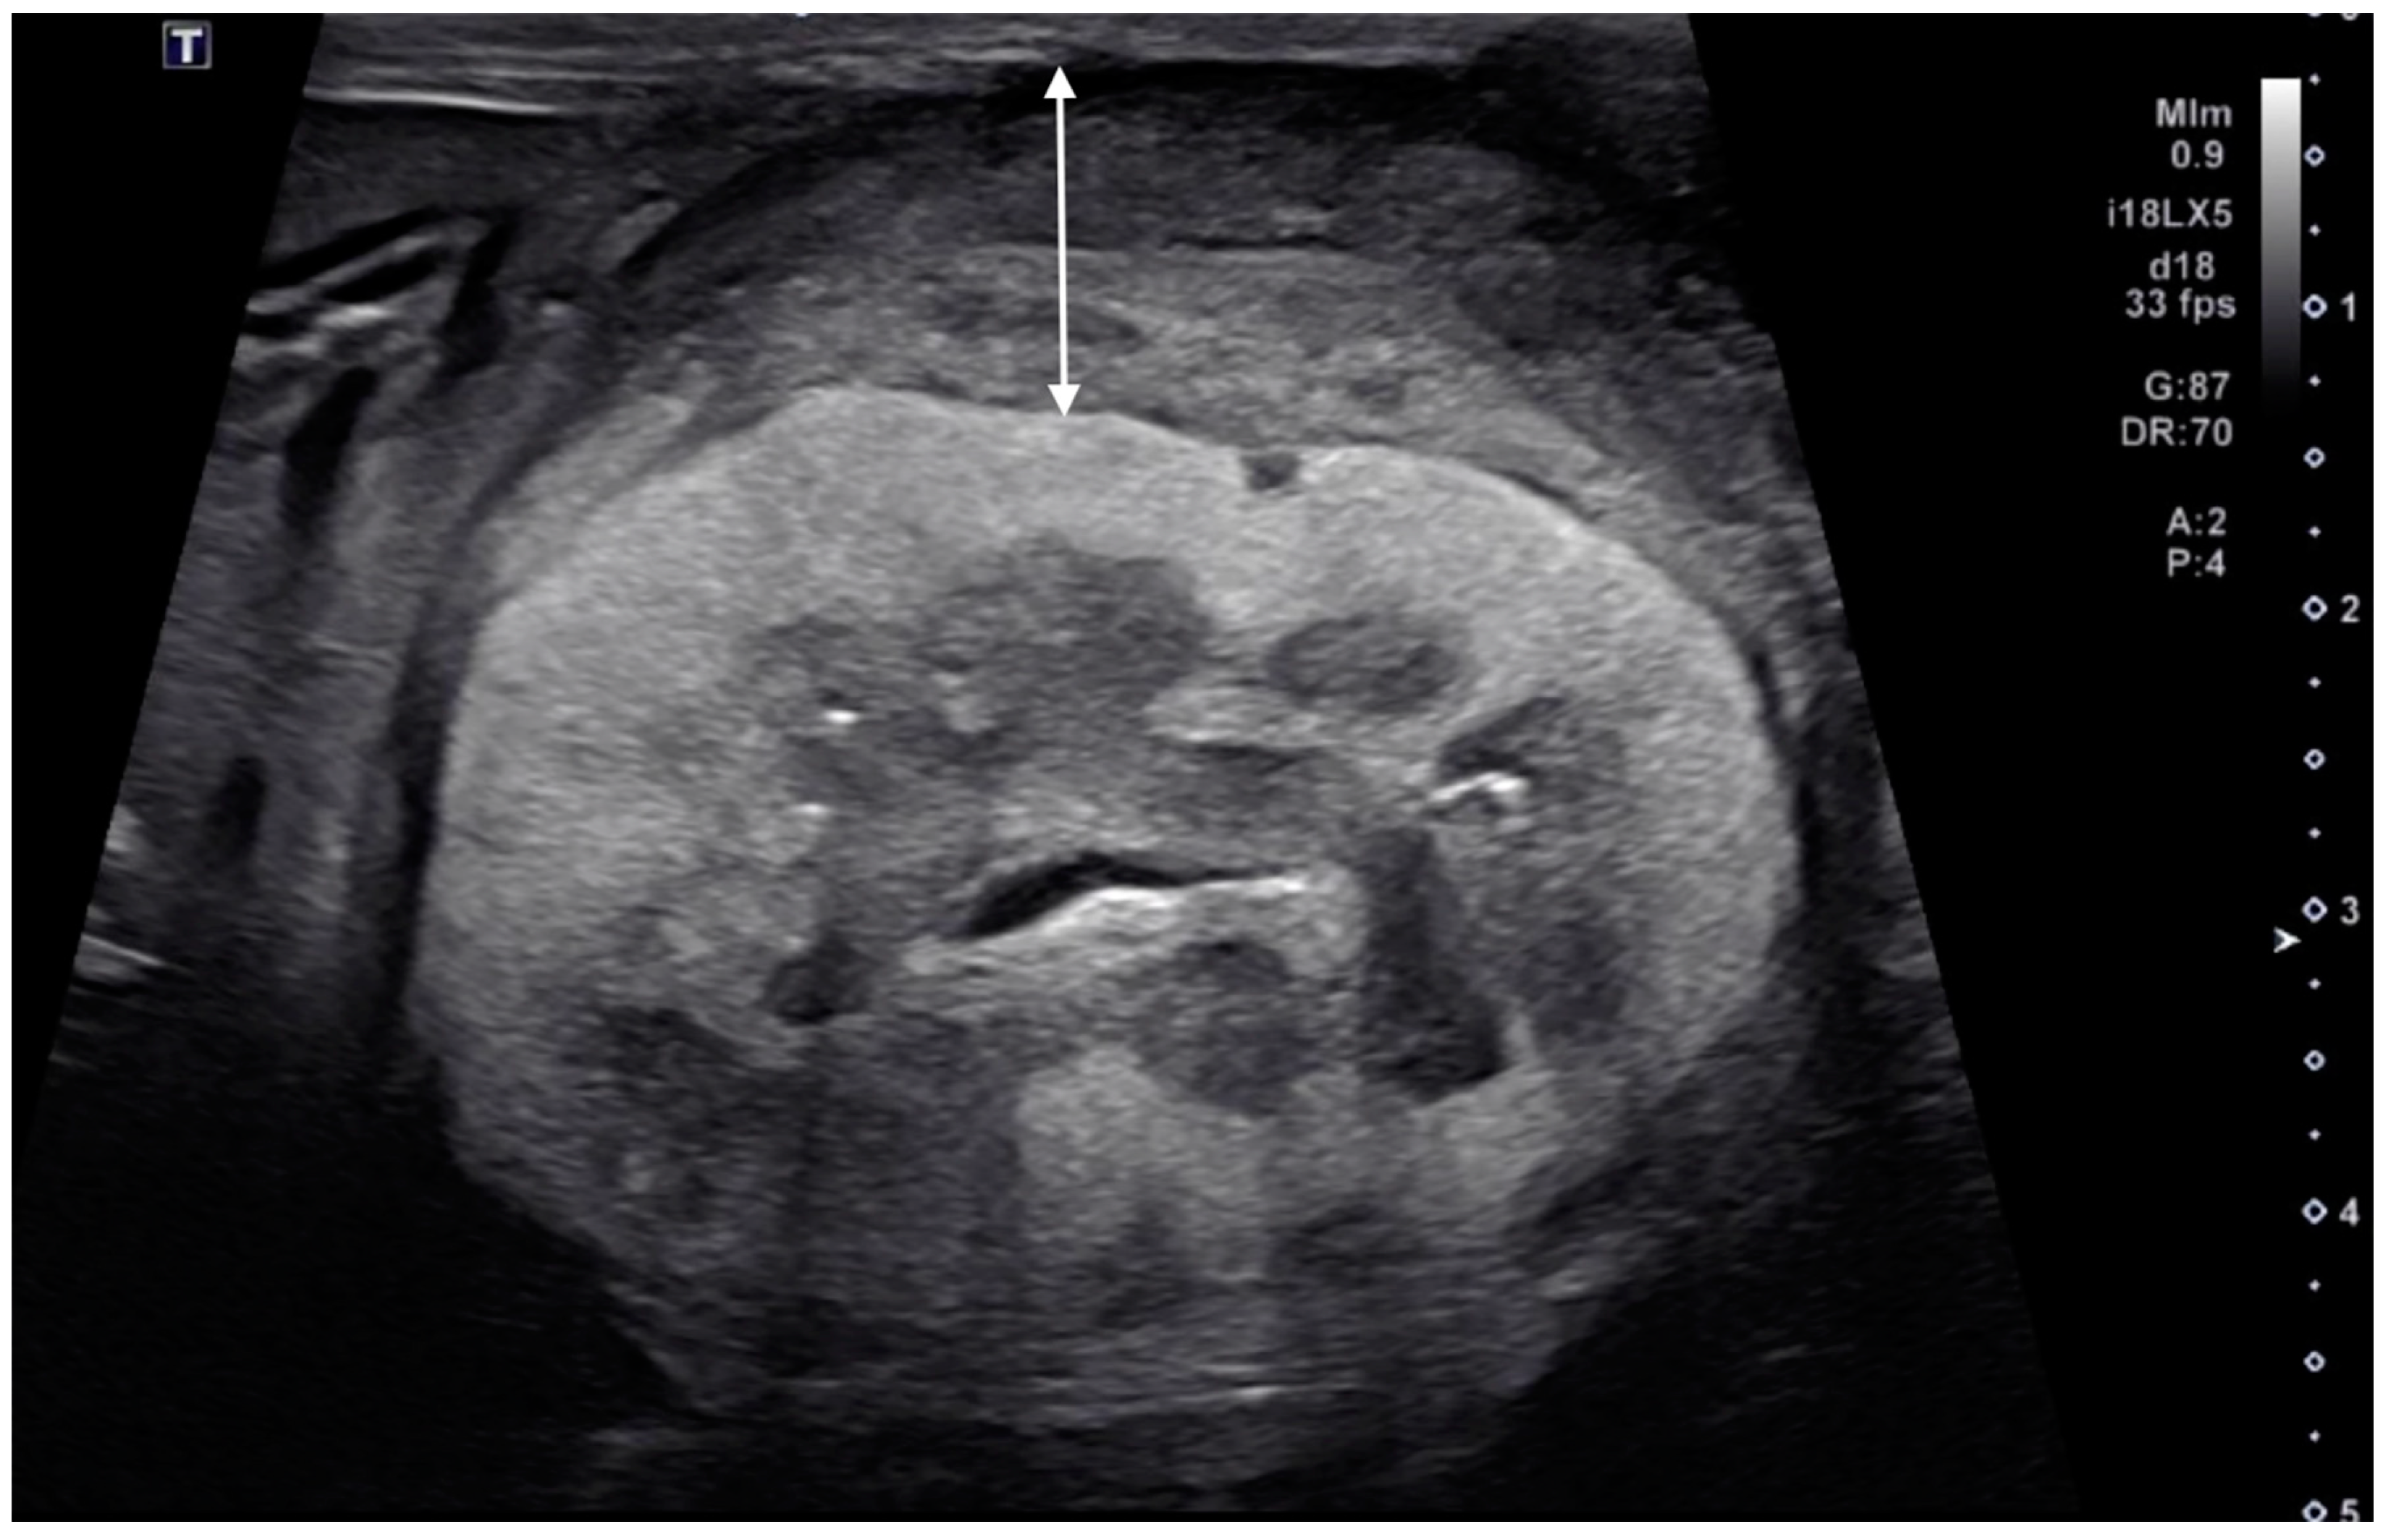

The renal cortical margin was smooth in five kidneys (5/9; Figure 3) and irregular in four kidneys (4/9; Figure 1, Figure 2 and Figure 4). The capsular margin was smooth in five kidneys (5/9; Figure 3) and irregular in four kidneys (4/9; Figure 1, Figure 2 and Figure 4). Blood flow was assessed in five kidneys using color Doppler. The vascularity was observed within the thickened subcapsular lesion in two kidneys (2/5). Perirenal effusion was only observed in one cat, bilaterally.

Figure 3. Ultrasonographic image of a kidney with metastatic pulmonary carcinoma (case 2, left kidney). A thin, homogeneously hypoechoic subcapsular thickening (arrow) was present. The renal cortical and renal capsular margins were smooth.